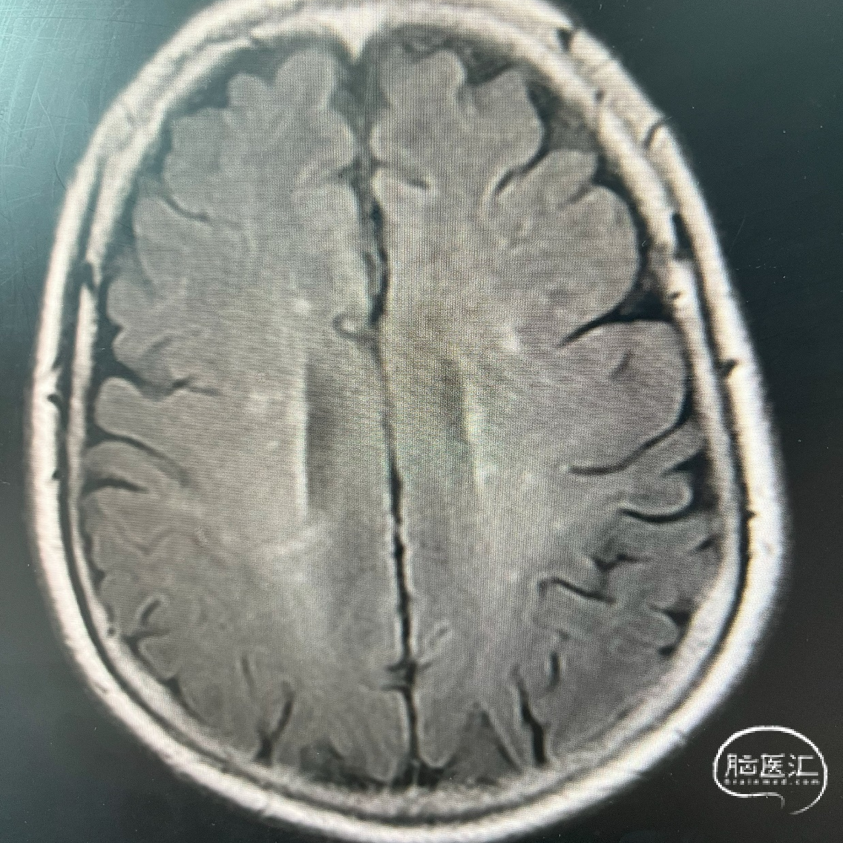

术前FLAIR

术前DWI

影像学表现: